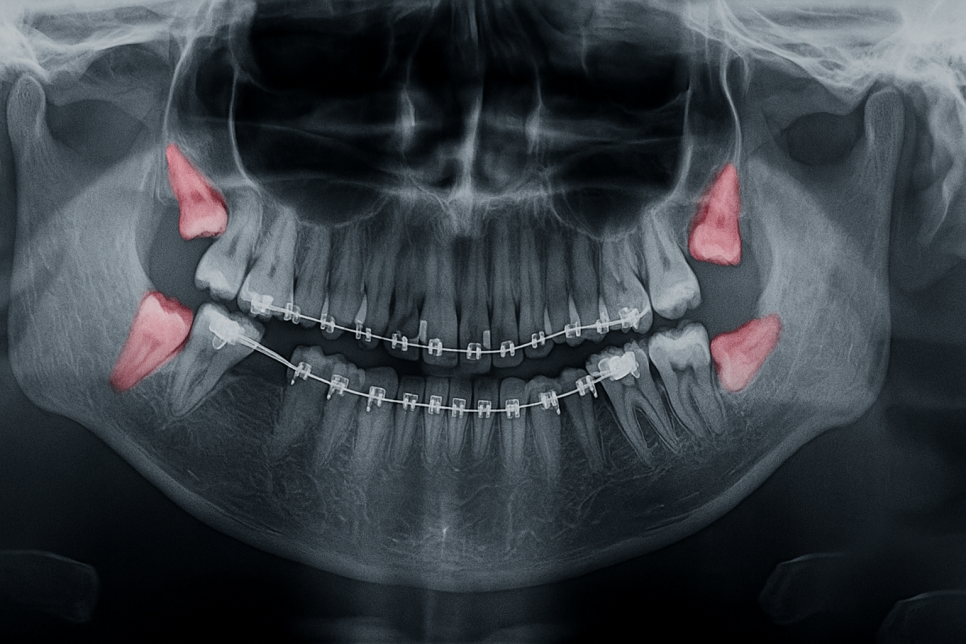

제3대구치는 어금니 옆,

구강 내 맨 안 쪽에 위치합니다.

인접 치아에 충치가 전염되어 있는 경우,

나아가 치주질환까지

이어져있을 가능성도 배제할 수 없습니다.